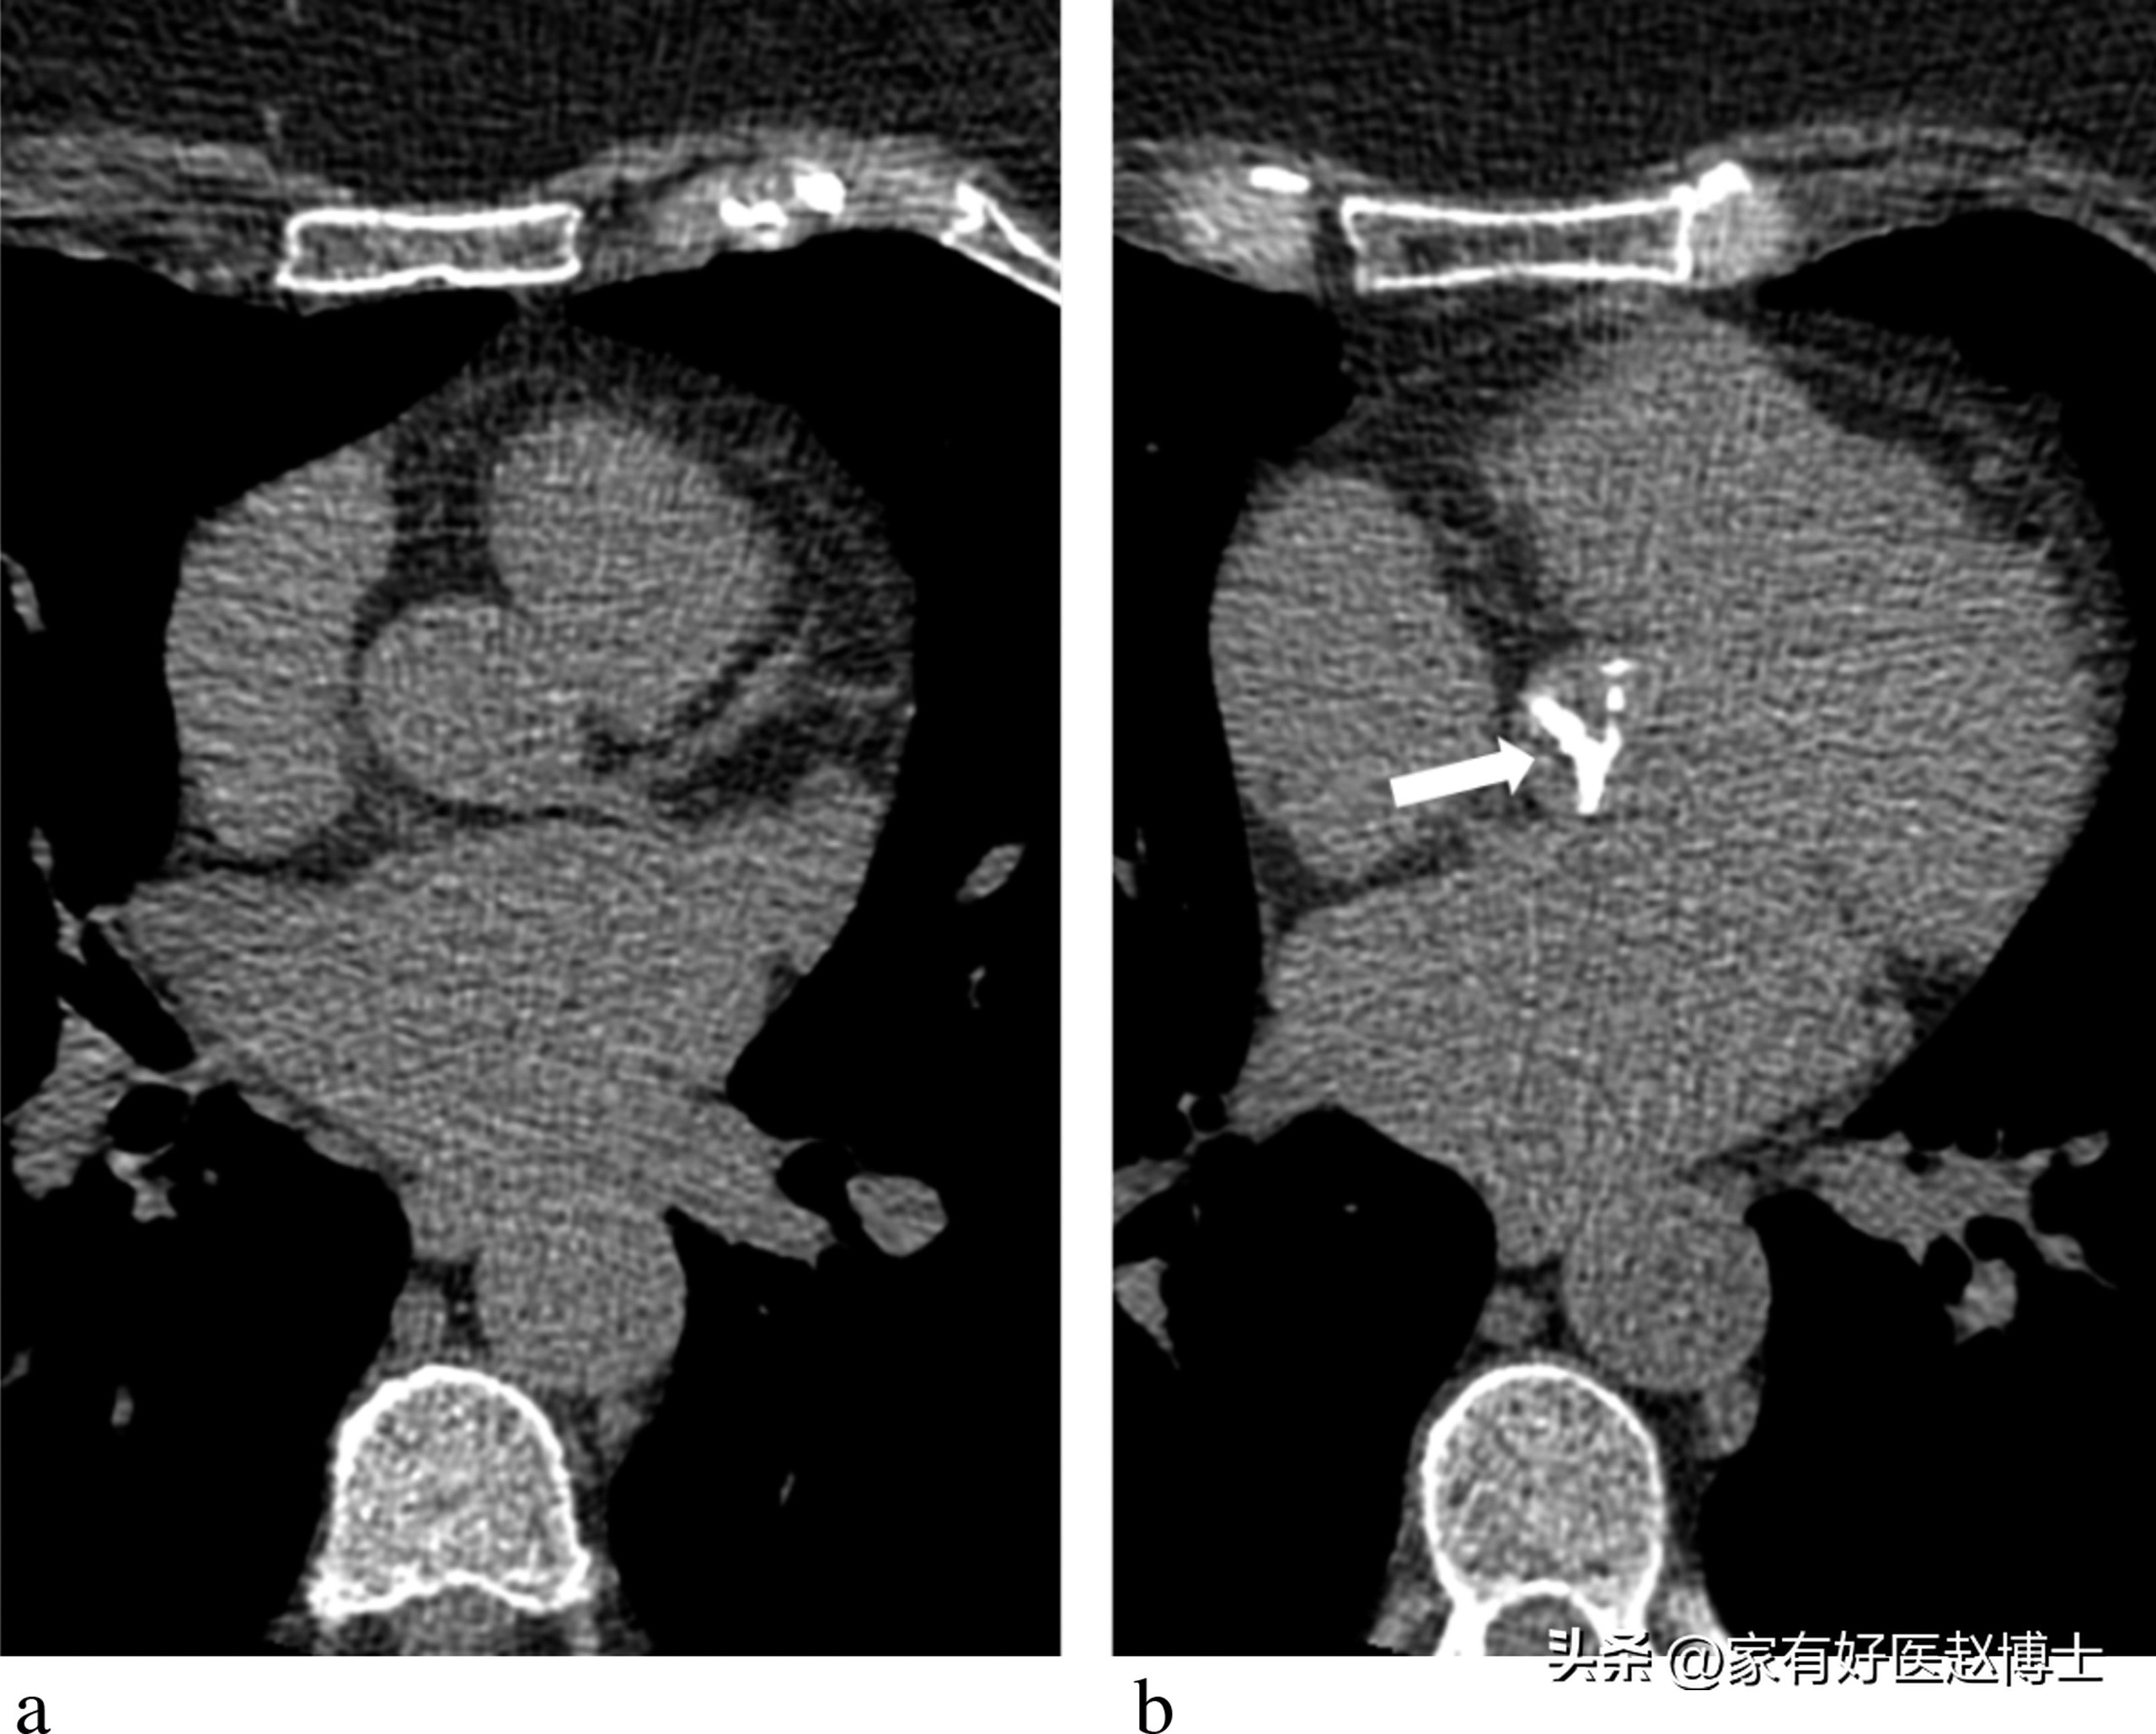

冠心病是“冠状动脉粥样硬化性心脏病”的简称。在临床上,诊断冠心病的“金标准”是要通过冠脉造影检查(CAG)来直接对冠状动脉血管进行成像,然后依据直观可见的血管狭窄程度来做判断。

根据《稳定性冠心病诊断与治疗指南》的定义:只有通过冠脉造影(CAG)“直接看到”血管的狭窄超过50%的时候,才可以确诊“冠心病”!

也就是说,即便冠状动脉上存在动脉粥样硬化,这也不代表可以确诊“冠心病”!只有当动脉粥样硬化引起冠脉狭窄超过一定的程度,才算是有冠心病。

所以,体检发现“冠脉钙化”并不等于有冠心病!有没有冠心病,关键取决于血管是否发生了严重的狭窄。